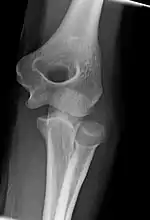

The elbow undergoes dynamic development of ossification centers through infancy and adolescence, with the order of both the appearance and fusion of the apophyseal growth centers being crucial in assessment of the pediatric elbow on radiograph, in order to distinguish a traumatic fracture or apophyseal separation from normal development. The order of appearance can be understood by the mnemonic CRITOE, referring to the capitellum, radial head, internal epicondyle, trochlea, olecranon, and external epicondyle at ages 1, 3, 5, 7, 9 and 11 years. These apophyseal centers then fuse during adolescence, with the internal epicondyle and olecranon fusing last. The ages of fusion are more variable than ossification, but normally occur at 13, 15, 17, 13, 16 and 13 years, respectively.[16] In addition, the presence of a joint effusion can be inferenced by the presence of the fat pad sign, a structure that is normally physiologically present, but pathologic when elevated by fluid, and always pathologic when posterior.[17]

There are three bones at the elbow joint, and any combination of these bones may be involved in a fracture of the elbow. Patients who are able to fully extend their arm at the elbow are unlikely to have a fracture (98% certainty) and an X-ray is not required as long as an olecranon fracture is ruled out.[27] Acute fractures may not be easily visible on X-ray.[28]